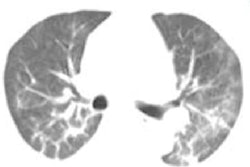

The team found that, overall, ground-glass opacities and consolidations were the main CT signs of COVID-19 disease. But there were some differences in CT findings by age, which included the following:

- Patients between the ages of 45 and 59 and those 60 and older had more bilateral lung, lung lobe, and lung field involvement, and greater lesion numbers than patients younger than 18.

- Ground-glass opacity along with interlobular septa thickening or a crazy-paving pattern, consolidation, and the air bronchogram sign were more common in patients between the ages of 45 and 59 and those 60 and older than in those younger than 18 or between 18 and 44.